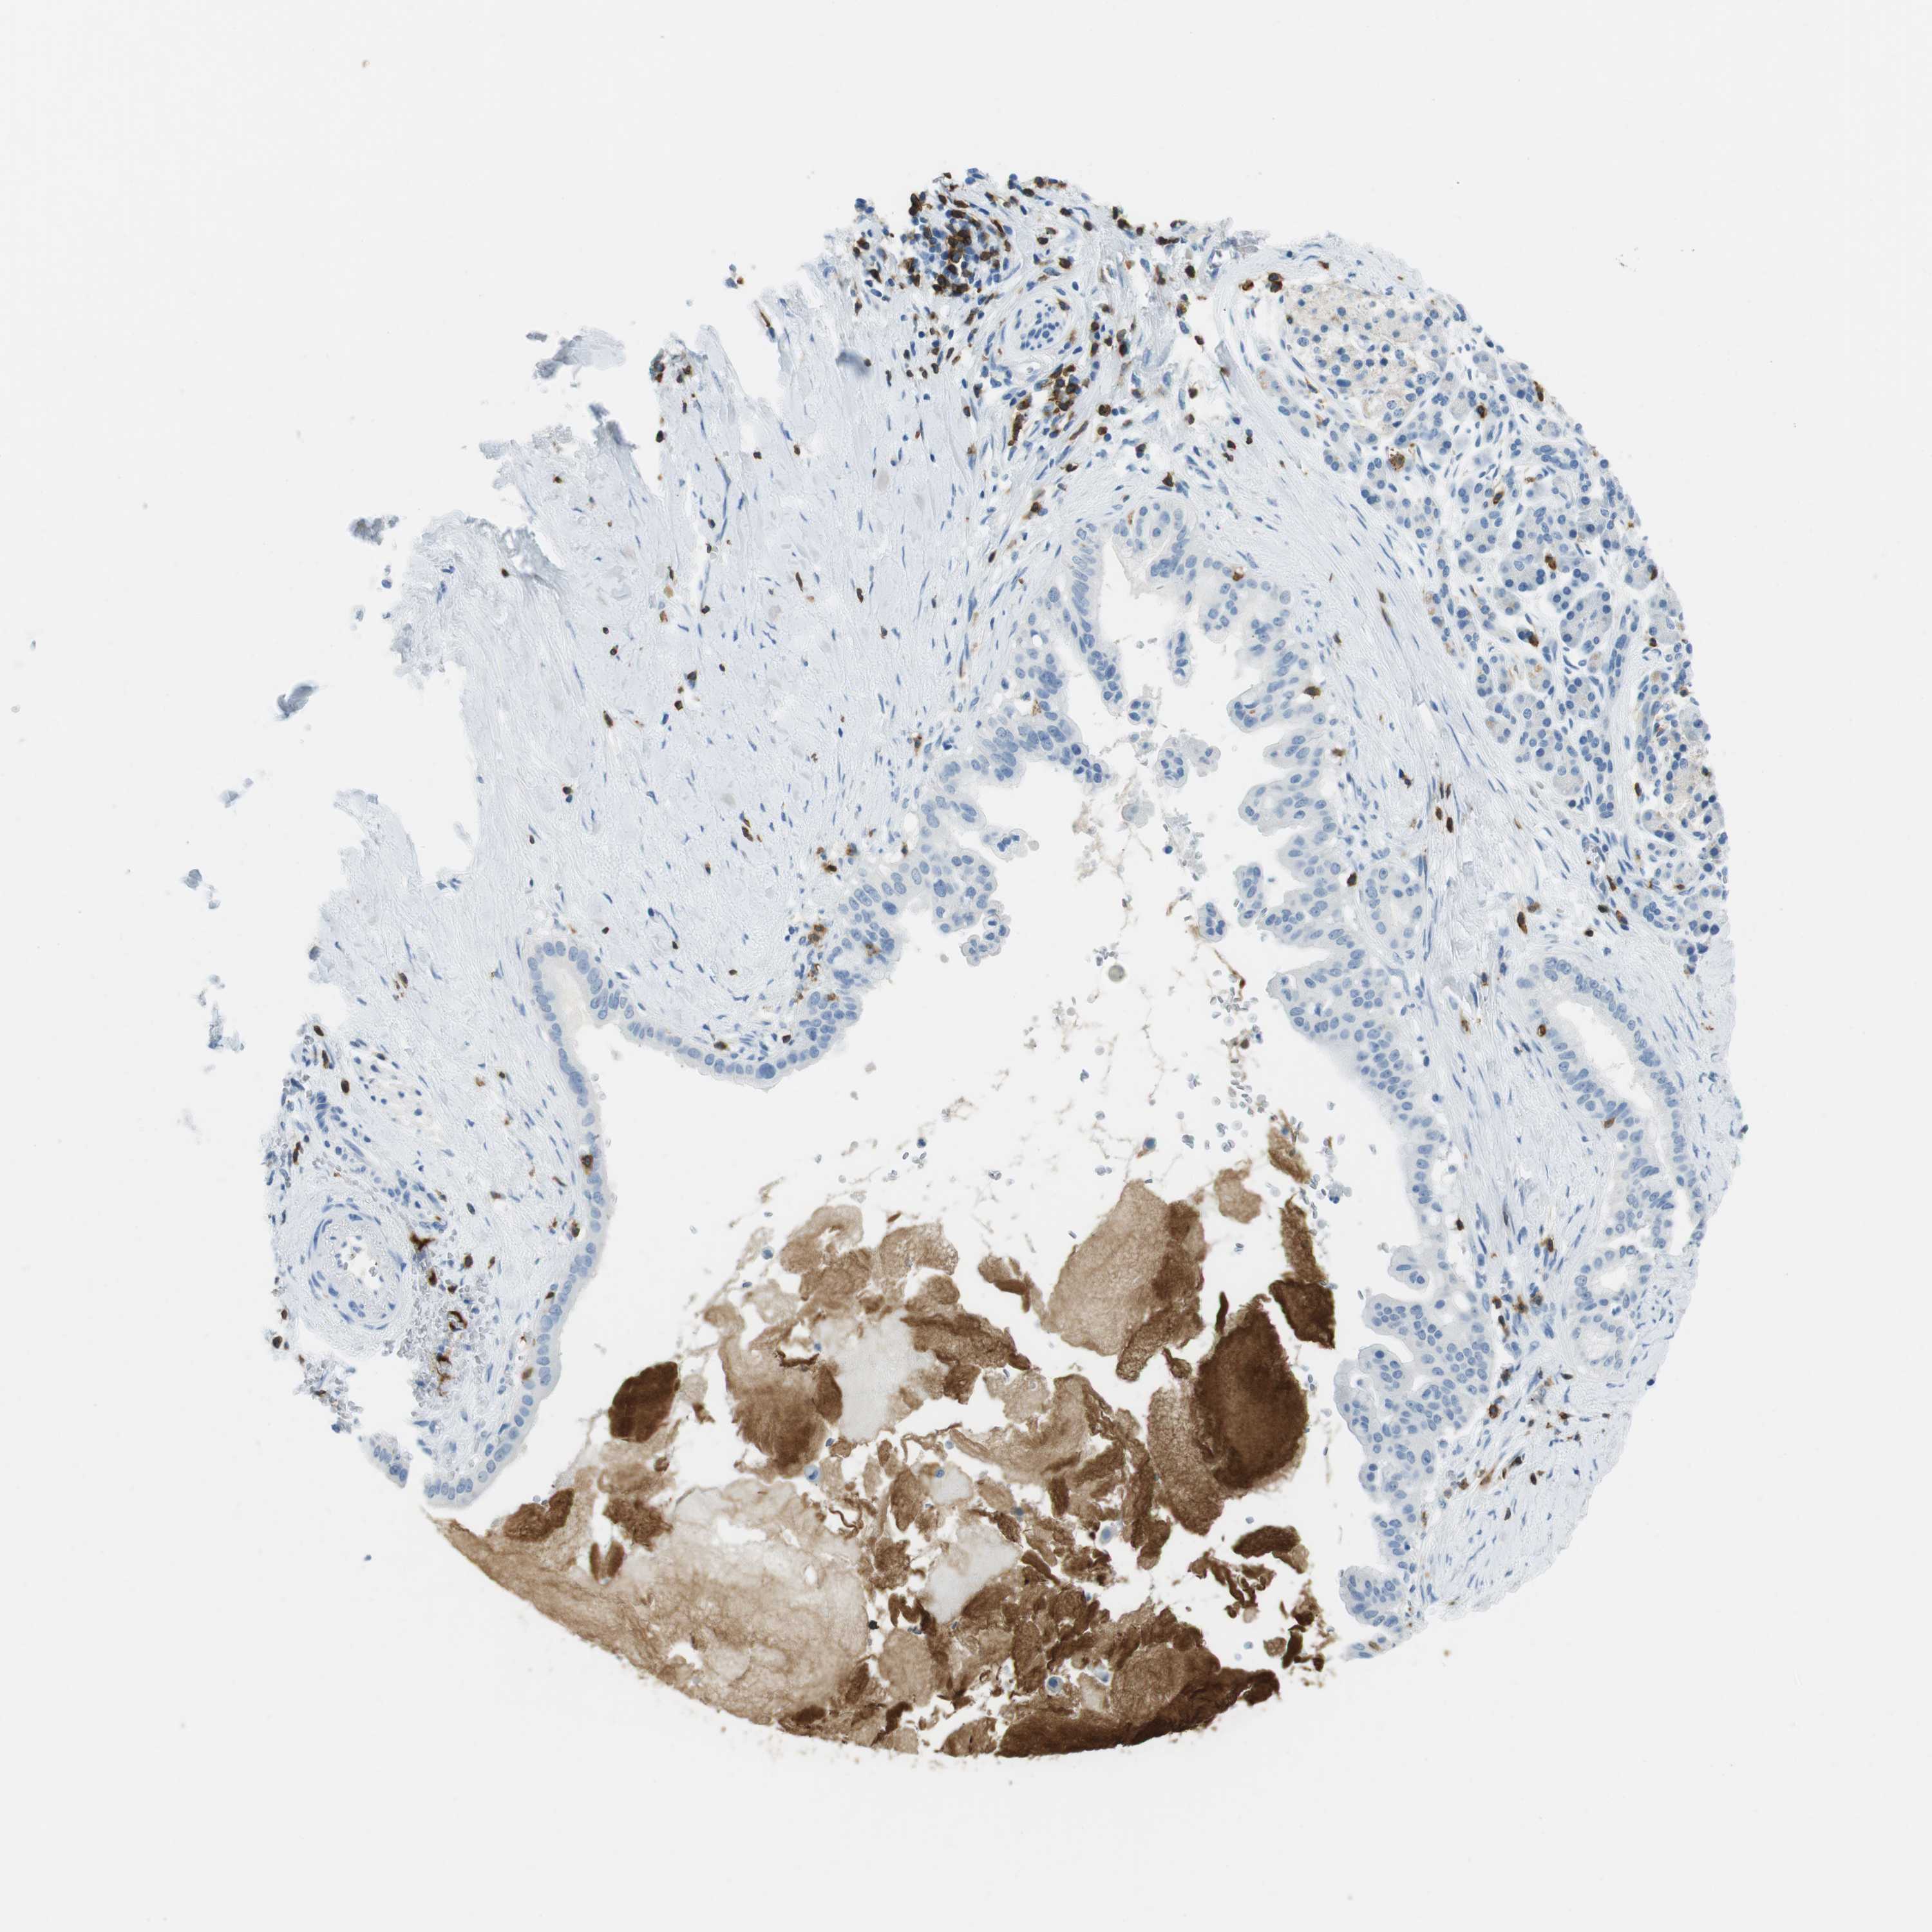

PANCREATIC CANCER - Protein expressioni

A mouse-over function shows sample information and annotation data. Click on an image to view it in a full screen mode. Samples can be filtered based on level of antibody staining by selecting one or several of the following categories: high, medium, low and not detected. The assay and annotation is described here.

Note that samples used for immunohistochemistry by the Human Protein Atlas do not correspond to samples in the TCGA dataset.

Antibody stainingi

Antibody staining in the annotated cell types in the current human tissue is reported as not detected, low, medium, or high, based on conventional immunohistochemistry profiling in selected tissues. This score is based on the combination of the staining intensity and fraction of stained cells.

Each image is clickable and will lead to virtual microscopy that enables deeper exploration of all samples and also displays staining intensity scores, fraction scores and subcellular localization as well as patient and tissue information for each sample.

Antibody HPA011157

Antibody CAB002223

Antibody CAB012978

Antibody CAB079960

Adenocarcinoma, NOS

Adenocarcinoma, metastatic, NOS